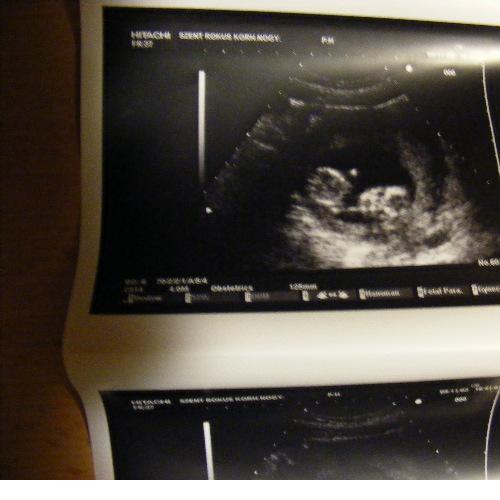

lonám! 9 centi?! Sőt, már nagyobb is. Váááóóó! Olyan hihetetlen, mi? Hogy vagy? Émelygés, hányinger? Elment már Tőled a róka? Lassan vége lesz ám a sokingeres időnek!

Donorúúúúú a kép!